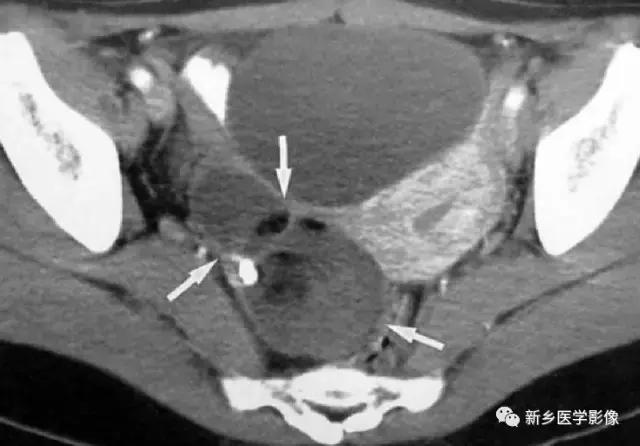

9、输精管钙化

主要表现为盆腔内对称性小钙化灶。